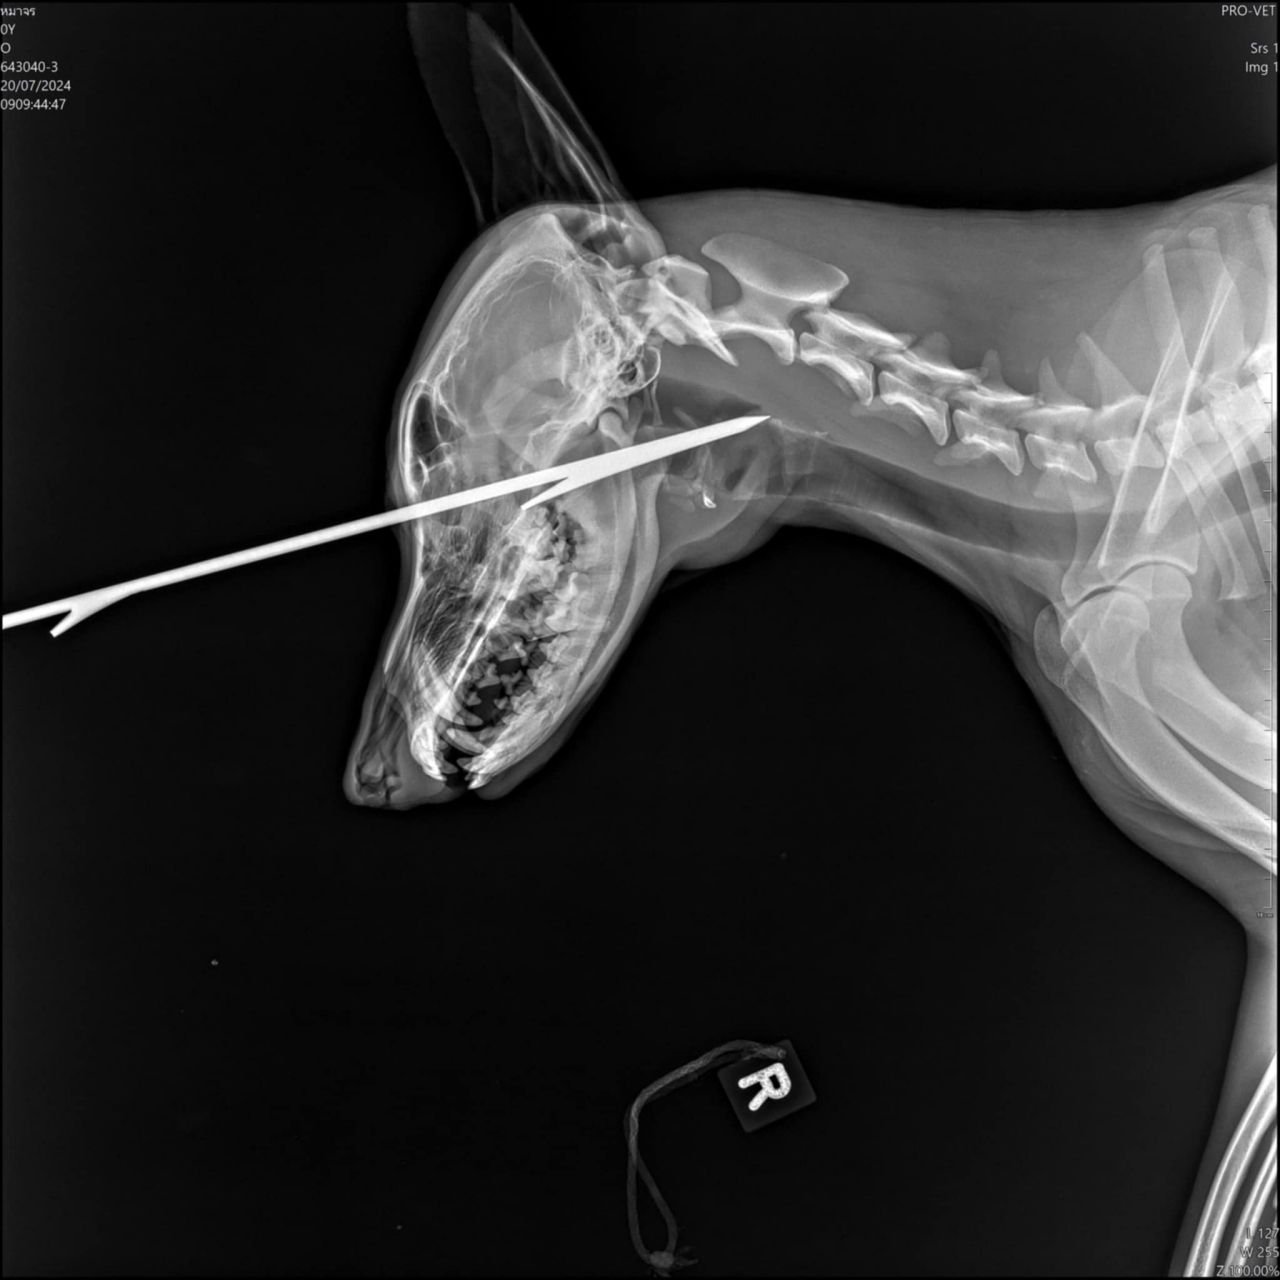

ทั้งนี้พบว่า ลูกดอกยิงปลามีที่เดียวตรงหน้าผาก โดยหมอจะตัดออกแล้วเปิดแผลอีกด้านเพื่อดันลูกดอกที่คาอยู่ให้ทะลุออก

โดยพบว่าลูกดอกดังกล่าวถูกยิงเข้ากลางหน้าผากถึงบริเวณลำคอยาวประมาณประมาณ 9 นิ้ว ตนต้องขอขอบคุณเพื่อนๆ พี่ๆ น้องๆ ผู้ใหญ่ใจดี ทาสรักน้องหมาน้องแมว และพี่ๆ กู้ภัย ต.นาบัว และผู้ที่มีส่วนเกี่ยวข้องทุกคนเลยที่เอ็นดูน้องหมาจรตัวนี้ โดยตอนนี้ตนขอรับเลี้ยงน้องไว้ที่บ้าน โดยชื่อให้น้องสุนัขใหม่ว่า "น้องศรรัก"